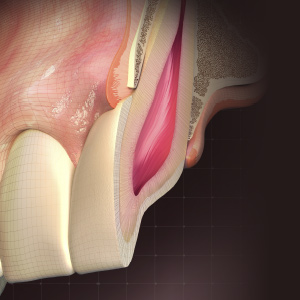

Implantology Advances

This Compendium eBook offers a continuing education (CE) article on partial extraction therapy in implant dentistry, with an emphasis on the biologic and anatomic conditions necessary for optimal outcomes with implant surgery. This eBook also includes a case report describing a strategy for...